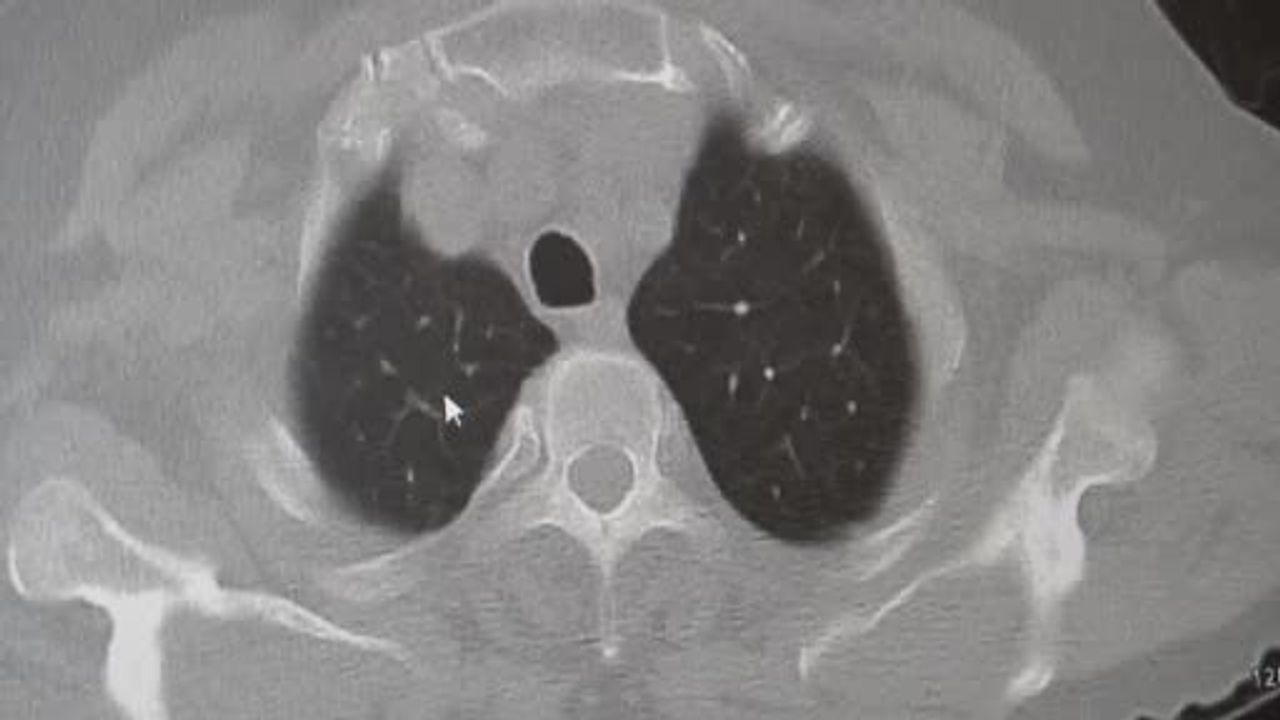

Karakurt, KOAH'ı zararlı maddelerin akciğeri tahrip etmesiyle ortaya çıkan bir hastalık olarak tanımladı. Buna ilişkin değerlendirmesinde, "KOAH önlenebilir bir rahatsızlıktır; sigaranın bırakılmasıyla birlikte tamamen ortadan kalkacaktır" ifadesini kullandı. Ayrıca hava kirliliği, iş yerlerinde kimyasal maddelere maruz kalma ve enfeksiyonların da KOAH nedenleri arasında yer aldığına vurgu yaptı.

Zatürre: Belirtiler, ayırıcı tanı ve riskler

Prof. Dr. Karakurt, KOAH'lı hastaların akciğer dokusu tahrip olduğunda enfeksiyonlara daha yatkın hale geldiğini ve enfeksiyonların daha güç geçebildiğini belirtti: "Akciğer dokusunun tahrip olduğu her durumda hastaların enfeksiyona karşı eğilimi artar ve enfeksiyona yakalandıklarında bunun geçmesi güç olur."

Zatürrenin belirtileri arasında öksürük ve balgam artışı, yüksek ateş (örneğin 38,5°C üzeri), artan nefes darlığı, titreme ve bilinç bozukluğu sayılabilir. Karakurt, bronşit ile zatürrenin ayırt edilmesinin önemli olduğunu; bronşitin daha çok bronşları, zatürrenin ise alveolleri (hava keseciklerini) etkilediğini vurguladı. Bronşitten ölüm nadirken, zatürrenin yaklaşık %10 civarında bir ölüm oranı ile seyrettiğini ve bu oranın yaşla birlikte arttığını kaydetti.